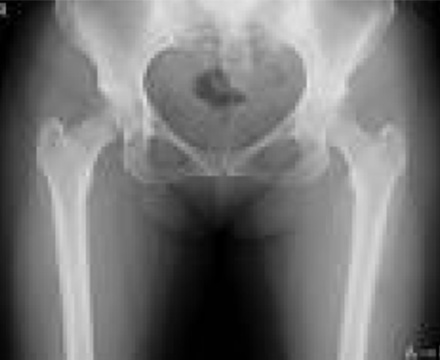

エックス線を利用して検査をするいわゆる“レントゲン撮影”です。

胸部、腹部、全身の骨の撮影を行います。心臓の大きさや肺の異常陰影、ガスの状態や骨の形、骨折の有無、関節の状態などがわかります。

当院ではフラットパネル(FPD)というシステムを導入し従来よりもエックス線の感度が高く低被ばくで撮影ができるようになりました。撮影効率も向上し撮影待ち時間も短縮しています。